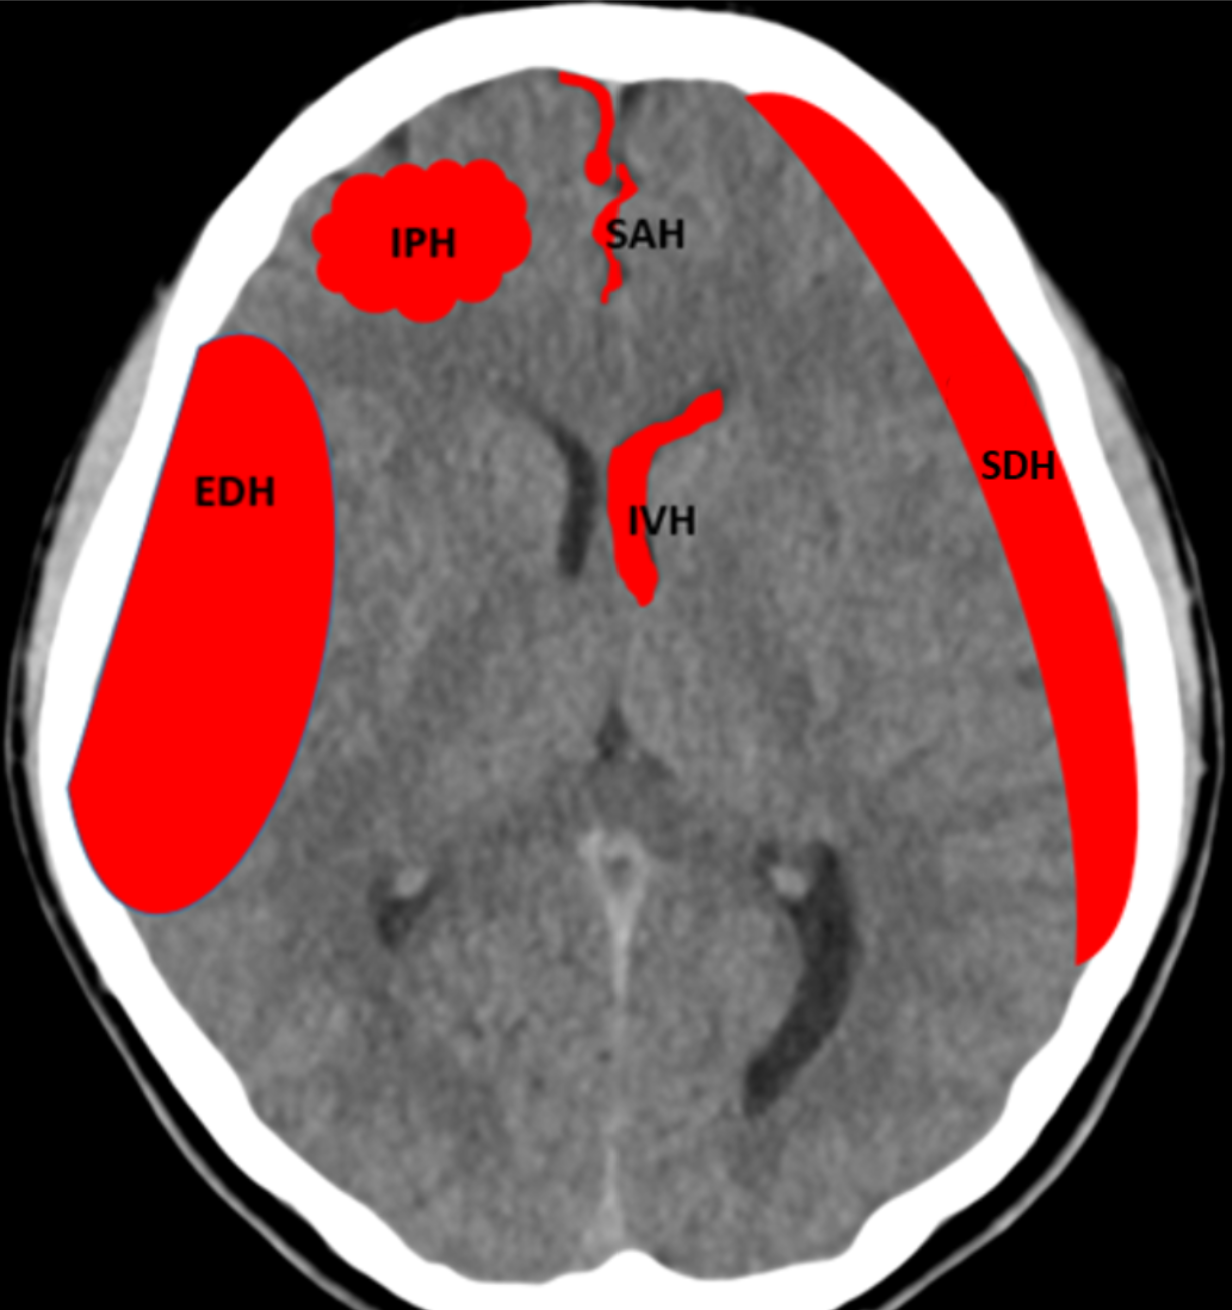

Demographic data were retrieved, including the time when: 1) CT was performed, and 2) the radiologist signed the report. Two patient groups were created based on whether an ICH was detected or not. Within the ICH detected group the clinician further classified the bleed etiology as being: epidural hematoma (EDH), acute subdural hematoma (SDH), subarachnoid hemorrhage (SAH), intraparenchymal hematoma (IPH), or intraventricular hematoma (IVH), as well as evidence of mass effect (Figure 1-b). As this was a live consecutive patient population other pathologies were also encountered and were classified as non-ICH with other pathologies i.e., tumor, non-hemorrhagic stroke, etc. All information was retrieved from PACS and the signed radiology report (Figure 1-c).

Figure 9 presents examples of true positive cases where VIOLA-AI successfully detected intracranial hemorrhage in CT scans. Specifically, (A) and (B) illustrate smaller ICH, (C) depicts acute SDH, (D) shows a combination of SAH, IPH, and IVH, and (E) highlights both acute SDH and SAH. These images showcase the model’s capability to accurately detect a range of hemorrhage types and volumes, underscoring its high sensitivity and precision in identifying positive cases.

Well known challenging factors for both radiologists and AI models are locating and diagnosing; small ICH like SAH and thin SDH right adjacent to the skull shown as examples in Figure 9, but again with error feedback the in-house models can be adjusted to and upgraded especially with an interactive platform like NeoMedSys. To have a high sensitivity often produces a number of false positives, some examples presented in Figure 10, in this dataset the most common presentations were either other pathologies such as tumors or calcifications, or small locations such as close to venous sinuses or calcified/thick dura in the midline. The two latter also pose challenges to radiologists, hence such false positives could be of benefit to bring focus to these areas. False negatives (Figure 11) are always worrisome when it comes to ICH. Detecting bleeds that need acute intervention such as surgery is not difficult for either AI or radiologists to detect, however, the challenge lies with the smaller bleeds, especially the small SAH where studies have shown that they pose no immediate threat to patients, diagnosing these at a later stage does not pose a risk [16]. As false negatives exist eliminates the fact of AI models reliably producing final reports. While our primary focus was overall ICH detection, we acknowledge that a more granular analysis across specific ICH subtypes (e.g., SAH, SDH vs. EDH) will be important in future work as our dataset expands. Furthermore, our deliberate use of a dedicated ’Negative Test Set’ enriched with hard cases was a key strategy to address data imbalance and improve specificity, as reflected in the performance gains from VIOLA-1 to VIOLA-3.